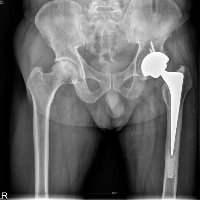

4) 고관절 전치환술

골괴사가 진행되어 골두 붕괴가 진행되었다면 가장 효과적인 치료는 고관절 전치환술이며, 손상 받은 연골 및 뼈를 인공 삽입물로 교체하는 것을 말합니다. 고관절 전치환술은 환자의 90~95%에서 통증 경감 및 기능회복을 가져오며, 가장 효과적인 수술적 치료방법으로 알려져 있습니다.

[고관절 전치환술(왼쪽): 대퇴 골두 및 비구를 인공 장치로 치환한 사진]